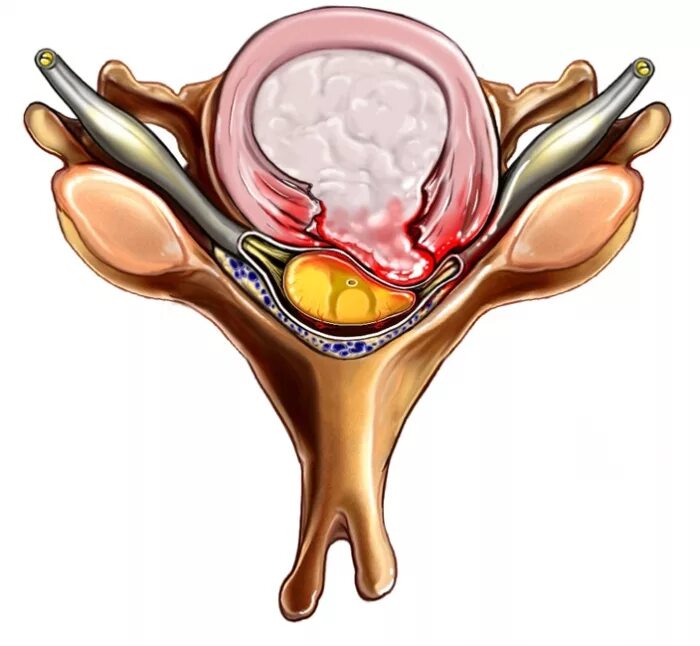

Диффузные кольца